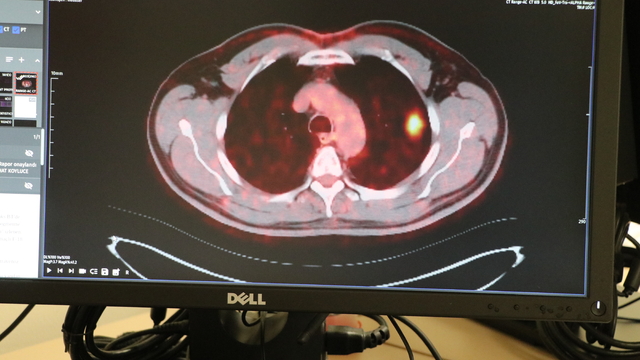

Kayseri Şehir Hastanesi Göğüs Cerrahisi Kliniği’nde görev yapan Doç. Dr. İbrahim Ethem Özsoy ise “Akciğer kanseri, dünya genelinde 2 milyon 200 bin civarında insanı etkiliyor. Bunlardan 1 milyon 800 bini de vefat etmekte. Türkiye geneline baktığımızda ise yılda 45-50 bin civarında akciğer kanseri vakası bildirilmekte. Akciğer kanserinde en önemli şey erken teşhis. Bazı hastalarda bizim hastamızda olduğu gibi erken evrelerde tesadüfen saptanıyor. En önemli hastaneye başvuru bulguları göğüs ağrısı, nefes darlığı, öksürükle ya da balgamla karışık kanlı balgam ve diğer sistemlerini etkilediyse uzak organ belirtisiyle hastalarımız gelebiliyor. Akciğer kanserlerinin yüzde 90 civarında kısmı sigarayla ilişkili ya da sigarayı bırakmış kişiler. Hastamız da 61 yaşında. 50 yıldır sigara içen bir hasta ve düzenli olarak da kontrollere giden bir hasta. Acil servisimizde çekilen tomografide yaklaşık 2 santimlik küçük bir nodül görülmüş. Biz bunu incelemeye aldığımızda kanser olduğunu tespit ettik” dedi.

Akciğer kanserinin 4 evreden oluştuğunu aktaran Doç. Dr. Özsoy, “Bunlarda kendi içinde gruplara ayrılır. Evre 1 ve 2 hastalar sınırlı hastalık olarak geçer ve cerrahiye uygundur. Evre 3’te çok az bir kısmı cerrahi yapılabilir. 100 hastaya akciğer kanseri tanısı koyuyorsanız ancak 20 tanesi cerrahiye uygun olarak karşımıza çıkıyor. Geri kalan yüzde 80’i ileri aşamalarda karşımıza çıkıyor ve cerrahi şansını kaybetmiş oluyor. Hastamız, erken evrede teşhis konulup tedavi edildiği için bundan sonra yaşamına normal bir şekilde devam edecek. Hiçbir kısıtı olmayacak. Muhtemelen kemoterapi bile almayacak. Uzun yıllar sigara içip de belli yaşın üzerine gelen hastalarımızın mutlaka yılda 1 defa akciğer tomografisi çektirmesi gerekiyor. Çünkü küçük lezyonlar akciğer grafisinde görünmeyebiliyor” diye konuştu.